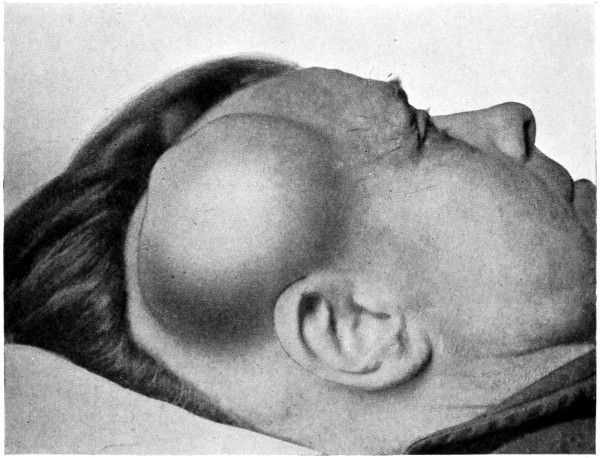

3. More rarely, the tumour overlies the anterior or posterior fontanelle. A case of this nature is depicted in Fig. 21, the tumour, situated over the anterior fontanelle, bulging over the temporal and frontal regions to a remarkable extent.

Sincipital cephaloceles are usually quite small, but the occipital variety and those situated in[35] the region of the anterior fontanelle frequently attain a great size (see Figs. 20-22).